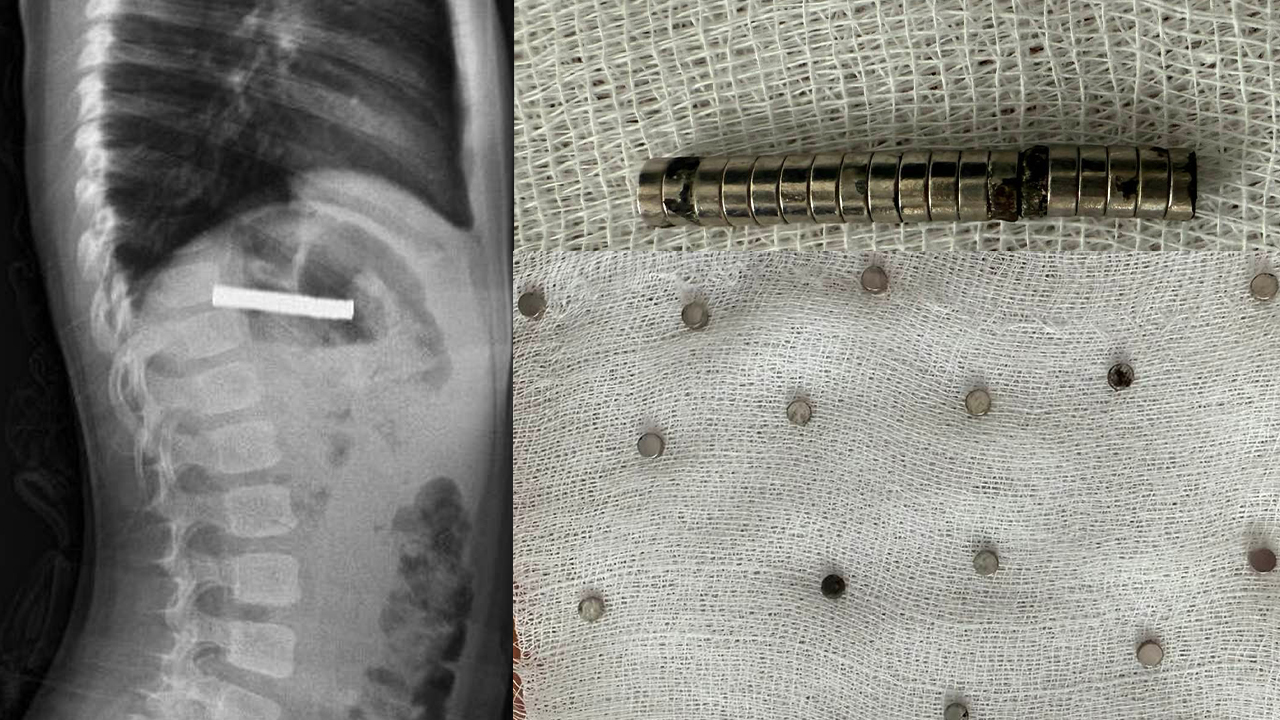

Elazığ’da 3 yaşındaki bir çocuğun yemek borusundan 19 tane mıknatıs çıktı!